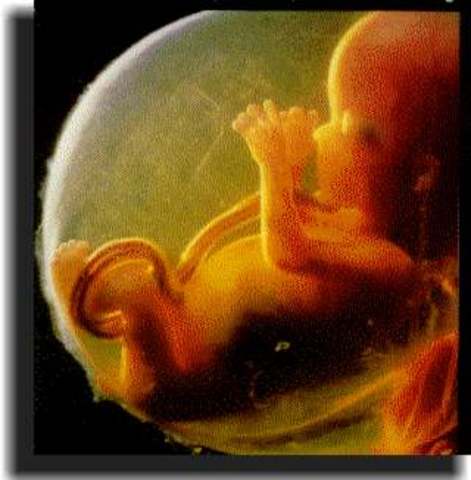

La mayoría de los sistemas orgánicos han concluido su formación. Los dedos están completamente desarrollados. A partir de aquí el embrión se va a denominar feto.

El cerebro crece rápidamente y alcanza el desarrollo completo. En la cara comienzan a apreciarse facciones humanas. Se han formado las cuerdas vocales y el feto es capaz de emitir sonidos. Aparecen las uñas. El feto muestra reflejos, su piel es sensible. Crece alcanzando 76 mm.

Por primera vez vas a sentir a tu feto, cuyos movimientos comienzas a notar. Podrás oír los latidos de su corazón. También se puede confirmar por ecografía el sexo.